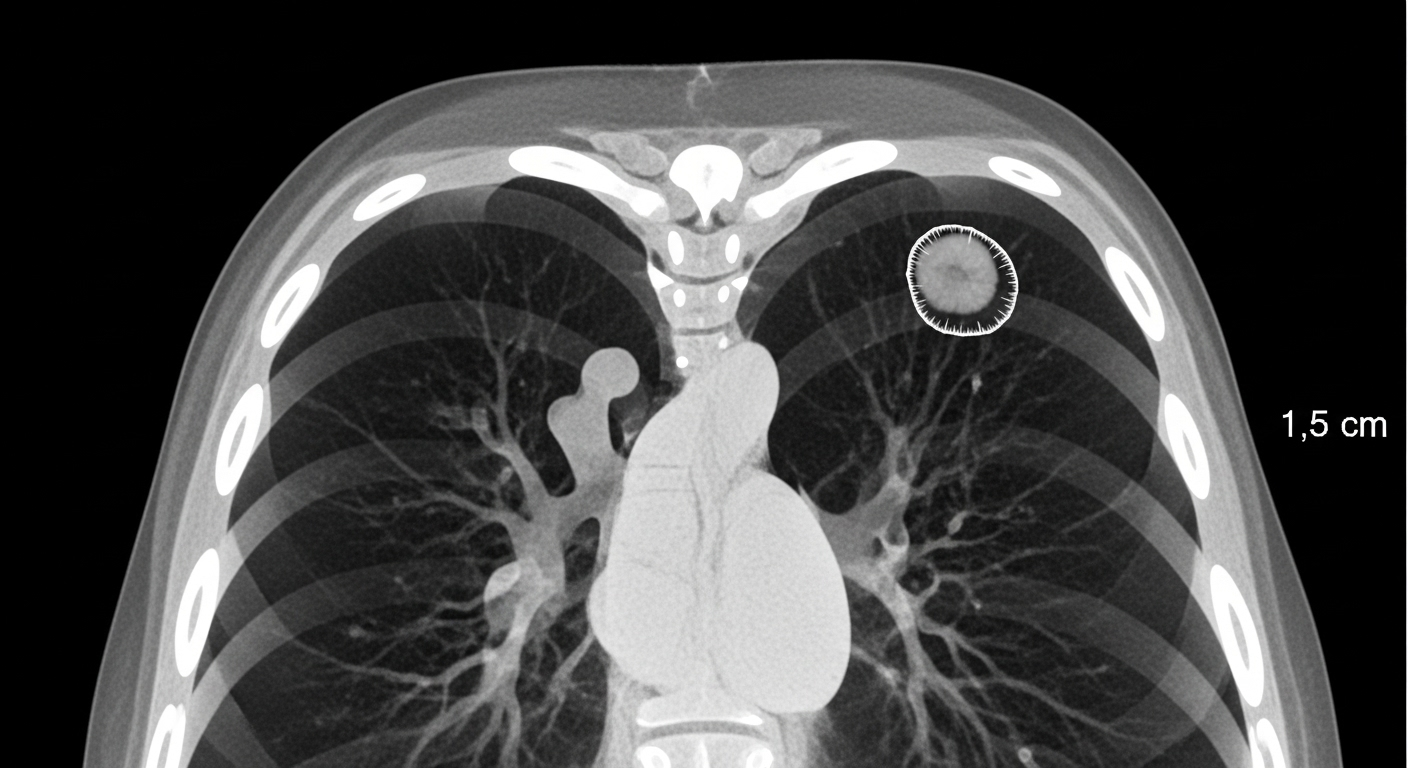

폐결절은 폐 내부에 생긴 지름 3cm 이하의 고립된 음영(덩어리)을 말합니다.

CT나 X-ray 검사에서 작은 동그라미처럼 보이며, 보통은 증상이 없습니다.

모양, 경계, 음영 정도에 따라 '고형 결절', '유리음영(GGO)', '부분 고형' 등으로 분류됩니다.